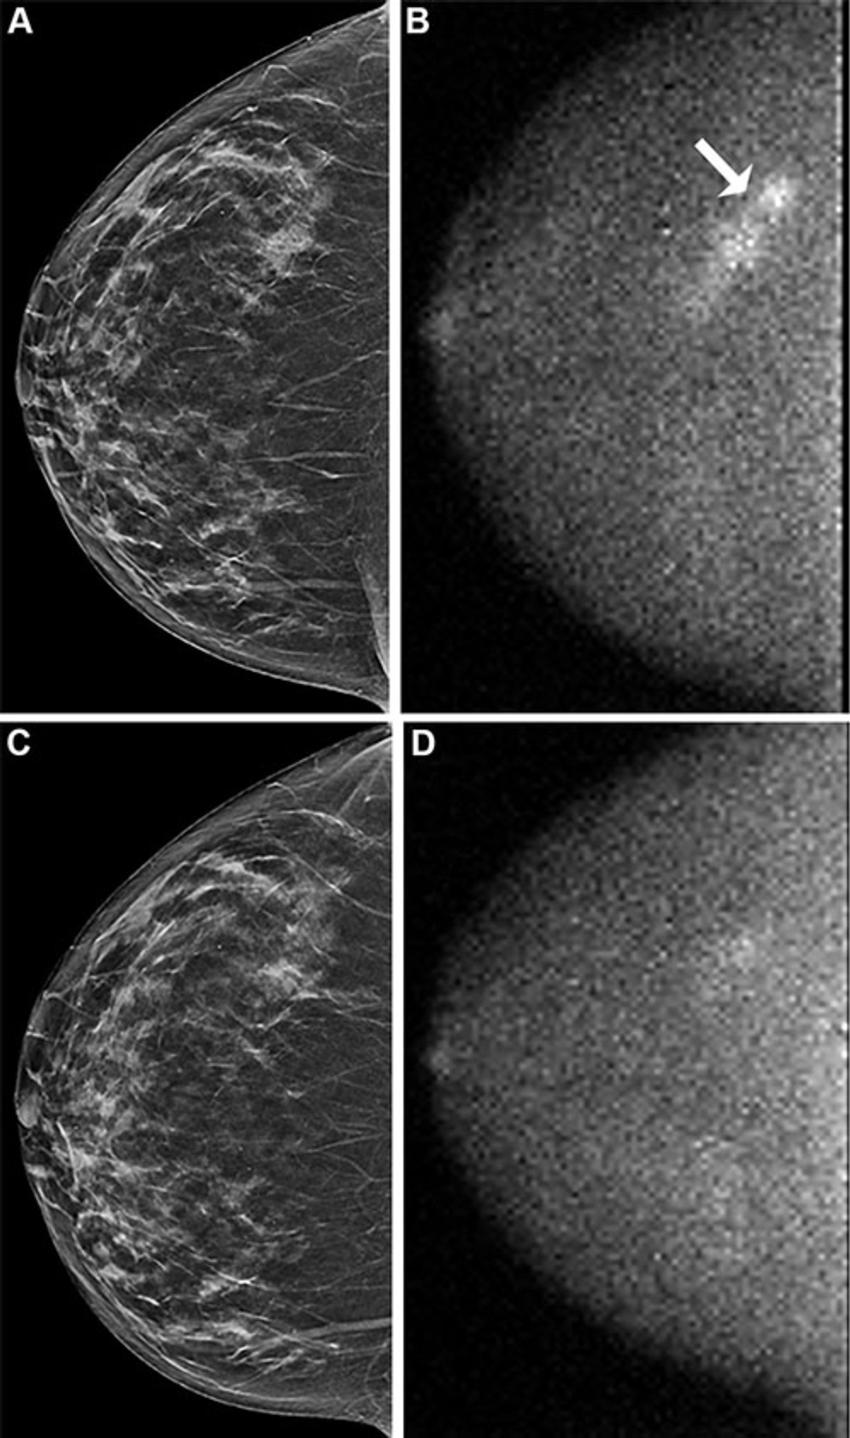

Figure 5. Images in a 69-year-old woman who presented for screening. (A) Image from digital breast tomosynthesis (DBT) screening (synthesized two-dimensional craniocaudal view of the right breast) at year 2 was negative and showing heterogeneously dense breast. (B) Molecular breast imaging (MBI) screening (right craniocaudal view) at year 2 shows a 4.7-cm nonmass focal area of uptake (arrow). US-guided biopsy and mastectomy revealed a grade 2 invasive lobular carcinoma, 9.1 cm in greatest extent, that was estrogen receptor positive, progesterone receptor positive, and human epidermal growth factor receptor 2 negative, with two sentinel nodes and 10 axillary nodes negative (N0). (C) Prior year 1 DBT was interpreted as negative. (D) Prior year 1 MBI was interpreted as negative with bilateral moderate background parenchymal uptake; a retrospective review revealed that mild uptake correlated with the location of the lesion detected at year 2.